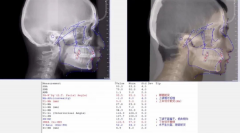

谢晓聪医生隐形矫治不对称拔牙案例分享

谢晓聪医生:矫正会改变下巴

很多人在矫正完后发现自己曾经的短下巴变长变好看了,有些人的下巴变尖变立...【详细】